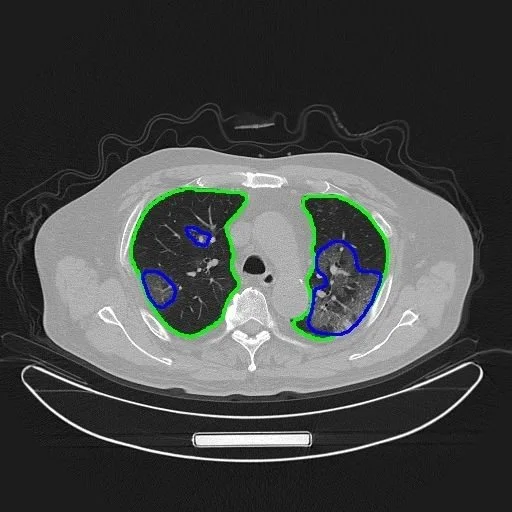

这种风气甚至被一些学者利用,来“忽悠”审稿人,“比如,为了体现论文的创新性,他们会在论文中写一些创新点,而在他们的算法实现中并没有都用到它们,或者起的实质作用并不大,实际上主要还是靠现有的深度学习方法或者加上一些小的implementation trick。另外,以图像分割的论文为例,有人在论文中不仅采用了深度学习,也用了传统方法对深度学习分割结果做了后处理,有时还能够显著改进深度学习直接得到的分割结果;但为了迎合做深度学习的审稿人,他们可能会轻描淡写甚至不提传统方法的作用,而是突出在深度学习框架里的创新点所起的作用。这几种文章发表以后,作者通常也不愿意公开所有的源代码。”

例如,医疗AI的训练数据,简单的“拷贝”并不能满足模型训练的需要,只有让医生耗费精力标注、分割才能在在模型上使用,这会耗费很大的成本,学术界很难做到。